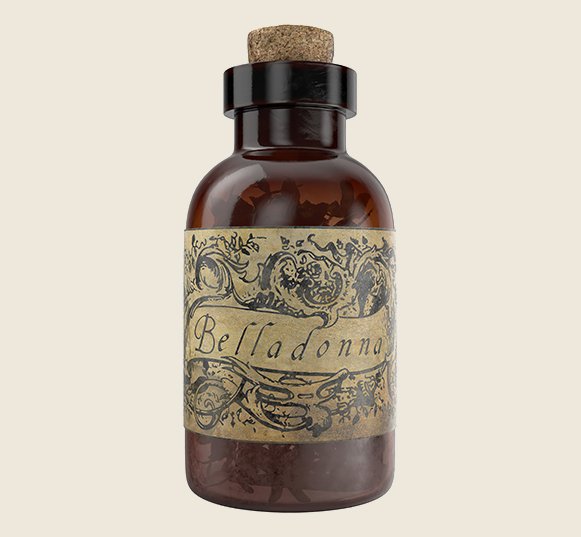

Яд для блеска глаз.

Как вам капли для глаз из белладонны? В Древней Греции ее использовали, как яд, а в 18-19 веках капли стали применять в Европе, как косметическое средство. Несмотря на то, что оно вызывало галлюцинации, слепоту, а длительное применение провоцировало летальный исход, женщины использовали его для расширения зрачков и блеска глаз.